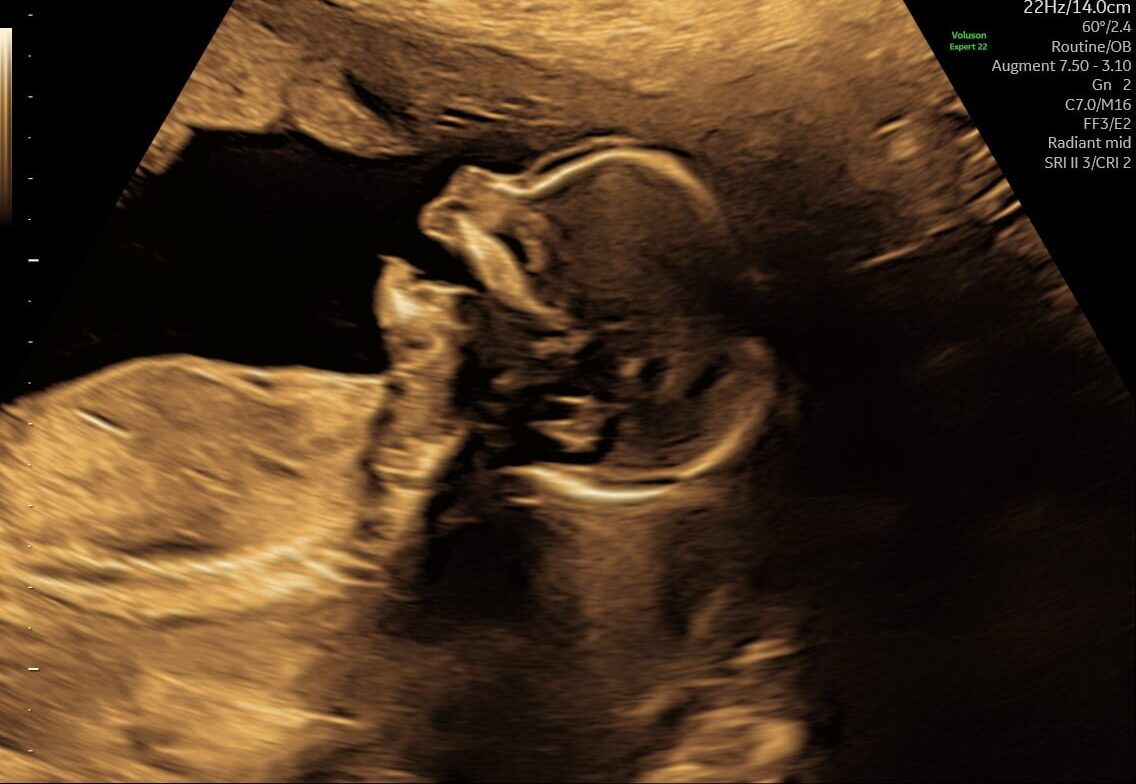

Hvad ser vi ved en tryghedsscanning?

Ved en tryghedsscanning fra uge 14+0 vurderer vi blandt andet:

- hjerteaktivitet

- bevægelser

- fostervand

- moderkagens placering

- generel trivsel

Hvordan foregår scanningen?

Tryghedsscanning foregår som en udvendig ultralydsscanning på maven. Vi guider jer undervejs og forklarer, hvad vi ser, så I får en rolig og forståelig gennemgang. Der er tid til spørgsmål, og vi fortæller altid, hvad der er normalt – og hvad der eventuelt bør vurderes videre.